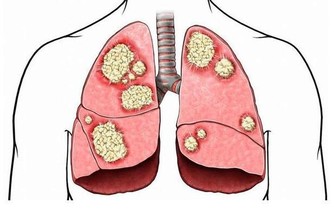

壹週刊報導,台大醫院新竹分院皮膚科醫師邱顯鎰表示,乾癬是一種自體免疫疾病,

患者如果感冒、壓力大,或生活上遇重大事件發生時,就容易誘發乾癬發作。